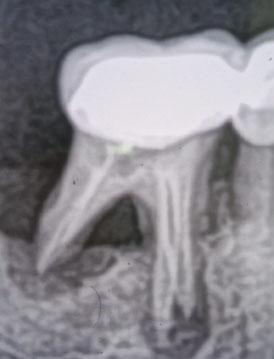

The dental X-ray shows a tooth with a crown and root canal treatment, with visible bone loss around the root area. The bone surrounding the tip and side of the root appears reduced, which indicates a previous or ongoing infection affecting the supporting bone.

This case shows bone loss around a previously treated tooth, a condition that requires careful monitoring. Early detection allows intervention before the tooth becomes non-restorable.